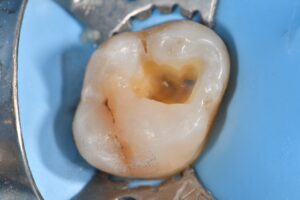

September 30, 2025 Class I direct resin using #KerrSimplishade Compressive strength: 366MPa (enamel 384MPa, dentin 297MPa) Flexural strength: 140MPa (dentin 165.6MPa) Previous Post Next Post